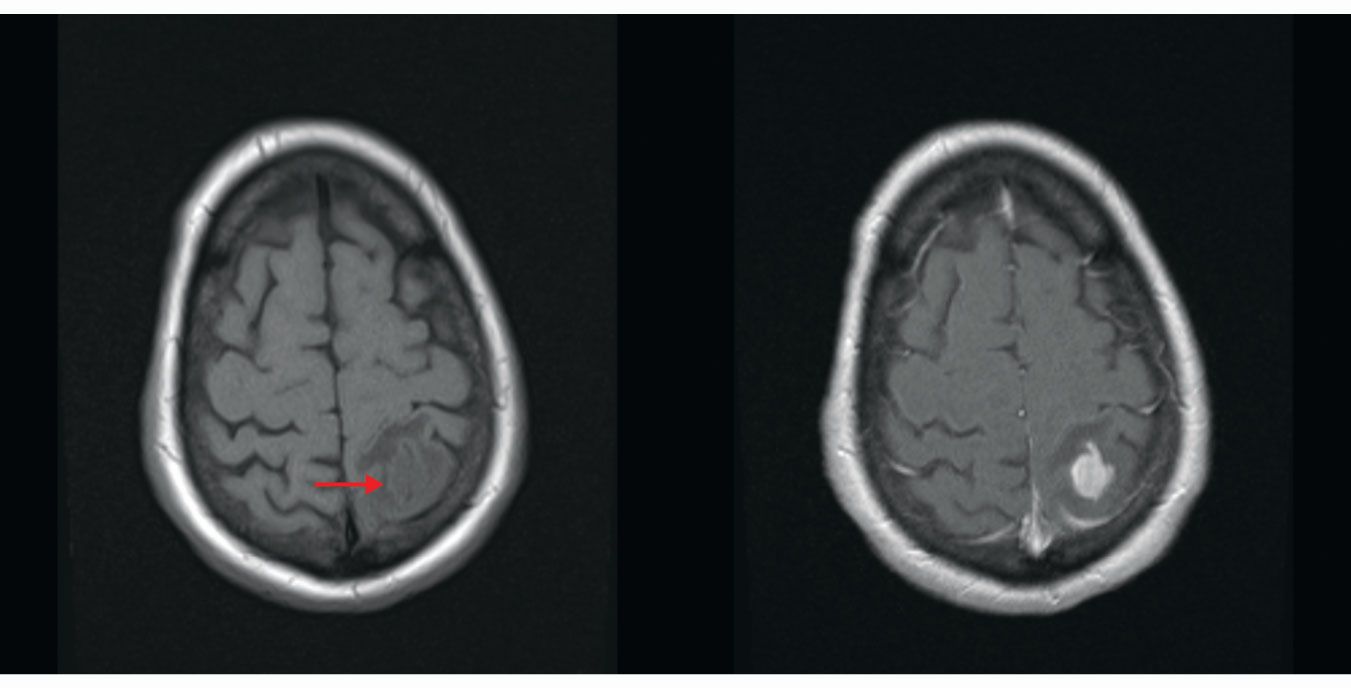

Figure 1.

MRI of a brain with T1 (left) and T2 (right) weighting. T1 refers to the time required for precessing nuclei in tissue to relax to their equilibrium orientation in a magnetic field, and T2 refers to the time it takes the nuclei to lose their phase coherence. The timing of RF pulses can be chosen so that the MRI signal comes from tissue with the shortest T1 times or the longest T2 times. Images taken with those different timings demonstrate how MRI can be tuned to produce different signal intensities in the same tissue. Fluid-filled ventricles (red arrow) are darker than the brain tissue on the T1-weighted image and brighter on the T2-weighted image. (Images by David Jordan, University Hospitals Cleveland Medical Center.)